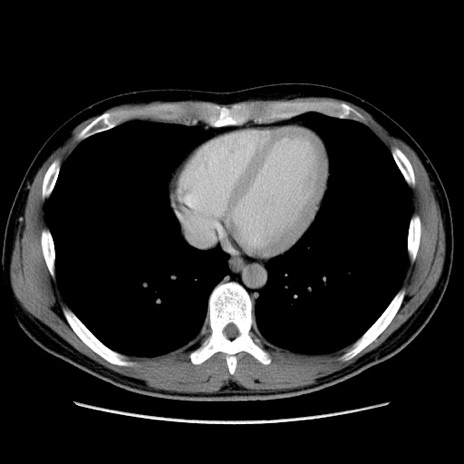

症例36(横断像)

【症例】20歳代 男性

【主訴】心窩部痛

【現病歴】今朝より上腹部痛あり。一旦軽快していたが再度出現したため救急要請。昨日夕に白身の魚を含む刺身を食べた。

【身体所見】BP 136/89mmHg、HR 74/min、BT 37.0℃、腹部:膨満、軟、心窩部に圧痛あり。反跳痛なし、筋性防御なし、腸雑音やや亢進あり。

【データ】WBC 17700、CRP 0.48